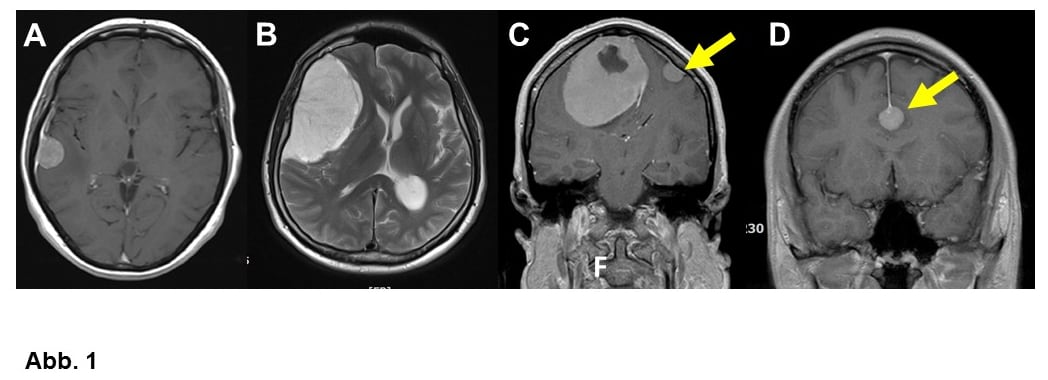

Von großer klinischer Bedeutung ist die Einteilung nach Lokalisation. Am häufigsten wachsen Meningeome ausgehend von der Hirnhaut über den Hemisphären (= Hirnhälften, Konvexitätsmeningeome, Abb. 1A-C) oder im Bereich einer bindegewebigen Sichel zwischen den Hemisphären (Falxmeningeom, Abb. 1C und D). Sogenannte Schädelbasismeningeome (Abb. 2, 3 und 4C) sind wegen ihrer Lage häufig schwieriger zu operieren als Konvexitäts- und Falxmeningeome. Meningeome können nicht nur ausgedehnt in den Hirnhäuten, sondern auch im Knochen (Abb. 4A und B) oder sogar vom Knochen ausgehend in die umgebenden Weichteile einwachsen (Abb. 4C). Meningeome im Bereich der Wirbelsäule (Abb. 5) sind seltener als im Kopf, sind aber umgekehrt häufige Tumoren im Rückenmarkskanal, wo sonst Tumoren eher selten sind. Bei bis zu 20% der Patienten liegen mehrere Meningeome vor (Abb. 1C).

Manche Meningeome werden im Anschluss an einem Krampfanfall diagnostiziert (Abb. 1B), kleine Meningeome sind ein häufiger Zufallsbefund (Abb. 1D), wenn aus ganz anderen Gründen ein CCT (Computertomogramm) oder MRT (Magnetresonanztomogramm) angefertigt worden ist. Große Tumoren können auch durch neurologische Symptome wie Sprachstörung, Lähmungen (Abb. 3C), Sehstörungen oder sogar Persönlichkeitsveränderungen auffallen (Abb. 1B). Bei entsprechender Lage kann ein Meningeom auch einmal den Hirnwasserabfluss stören und zu einem Wasserkopf (Hydrocephalus) führen. Kopfschmerzen sind häufig, selten aber durch den Tumor verursacht.

A. Kleines Konvexitätsmeningeom bei einer 48-jährigen Frau.

B. 57-jähriger Mann mit einem großen Konvexitätsmeningeom, das mit einer milden Persönlichkeitsveränderung auffiel. Im weiteren Verlauf erlitt der Patient einen Krampfanfall.

C. 55-jährige Frau mit einem sehr großen Falxmeningeom, zusätzlich kleines Konvexitätsmeningeom auf der Gegenseite (Pfeil). Bis zu 20% aller Meningeompatienten haben mehr als einen Tumor.

D. Zufallsbefund: Kleines Meningeom am Unterrand der Falx (Pfeil) bei einem 28-jährigen Mann.